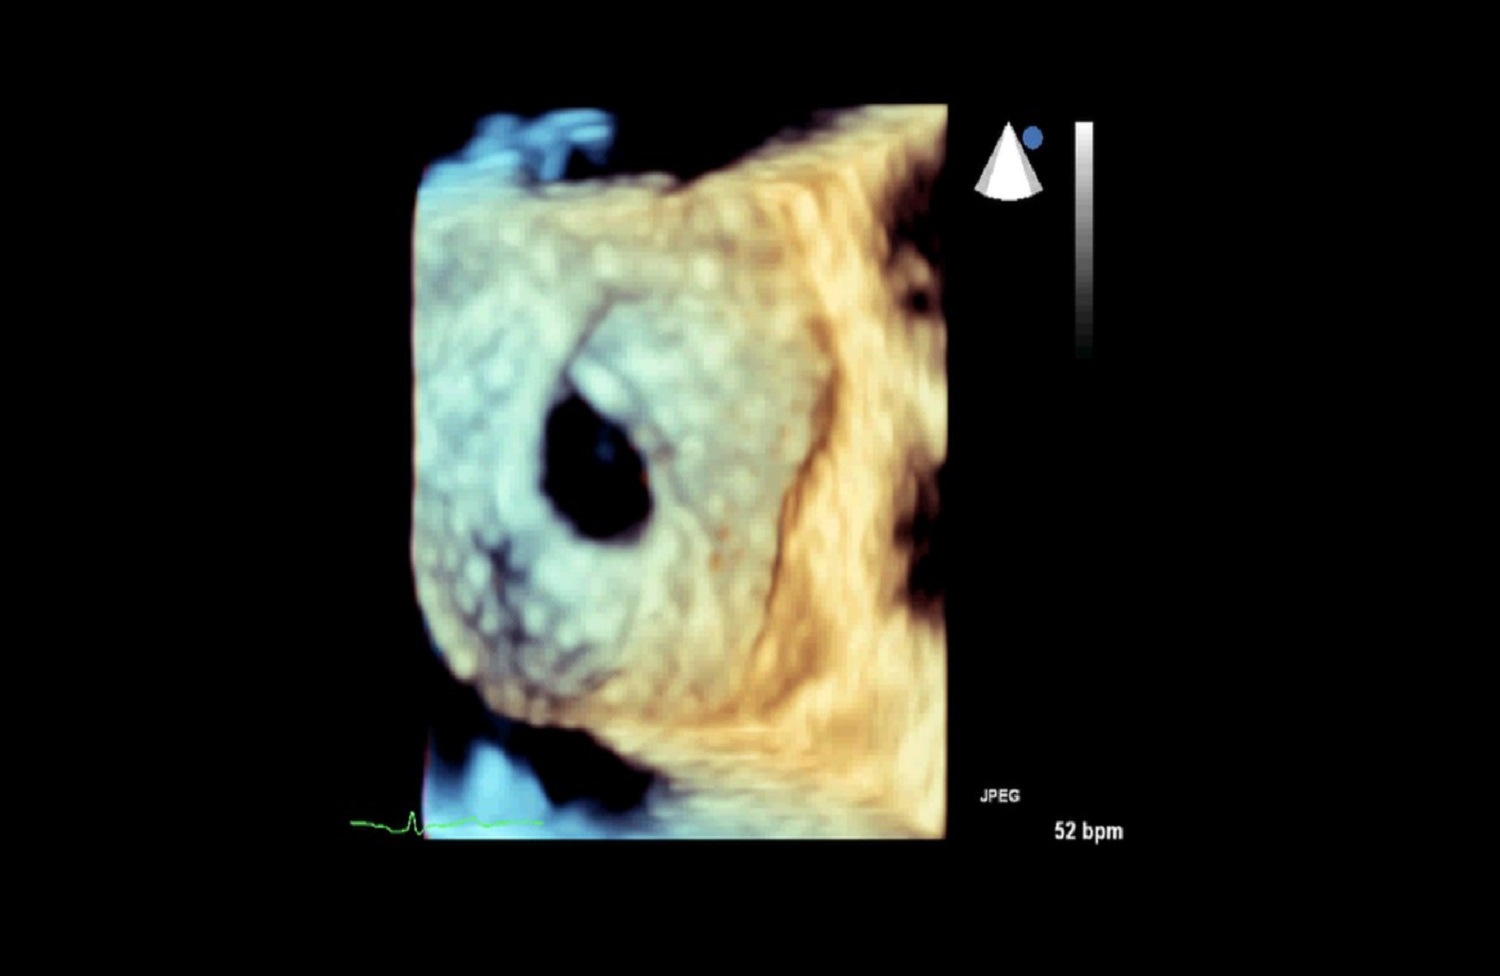

Wspólnie z pracownią echokardiografii naszej Kliniki, przy wsparciu Kliniki Anestezjologii WUM wykonujemy przezskórne zamknięcia przetrwałego otworu owalnego (PFO), ubytków w przegrodzie międzyprzedsionkowej (ASD) oraz przegrodzie międzykomorowej (VSD).

Zabiegi w wadach strukturalnych serca:

- przezskórne zamknięcia ubytków przegrody międzyprzedsionkowej (ASD);

- przezskórne zamknięcie ubytków w przegrodzie międzykomorowej (VSD);

- przezskórne zamknięcie drożnego otworu owalnego (PFO).

Dzięki wykwalifikowanemu personelowi i nowoczesnemu sprzętowi w Klinice wykonywane są również przezskórne zabiegi zamknięcia ubytków przegrody międzyprzedsionkowej typu II oraz drożnego otworu owalnego, pod kontrolą echokardiografii dwu – i trójwymiarowej.